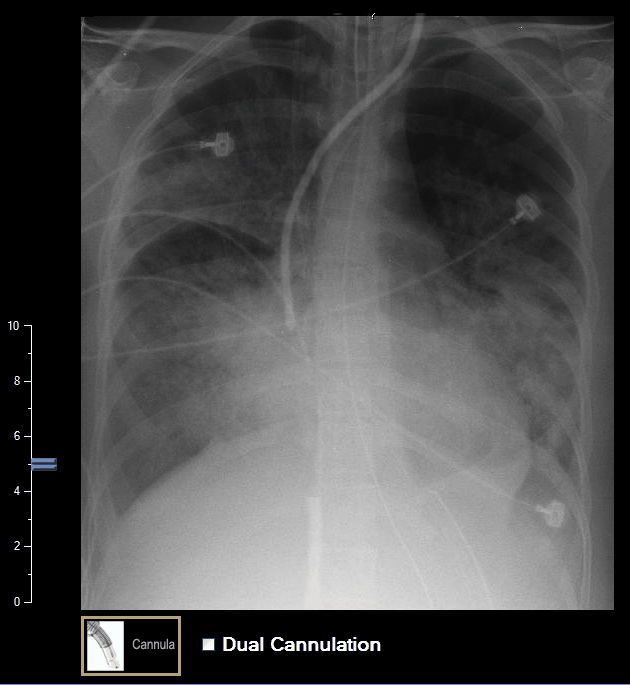

Cannula Adjustment Interface:

The cannula adjustment interface is used to advance or withdraw the femoral drainage catheter using the slide-control at the left. If the tips of the drainage and return cannulae are positioned too closely, re-circulation will start to occur and oxygenation will be impaired.

If satisfactory conditions cannot be obtained using a single drainage cannula, the 'Dual Cannulation' box should checked, and a second slide will appear which will enable the positioning of a second (SVC) cannula.